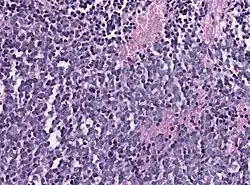

Biopsy is required for diagnosis. Pineoblastomas appear as high grade, highly cellular, small blue cells histologically. Features of aggressive malignancies can be seen, like high nucleus-to-cytoplasm ration, poorly differentiated cells, high mitotic activity, and necrosis.[13][3] Homer Wright, or neuroblastic, and Flexner-Wintersteiner, or retinoblastic, rosettes can also be seen. In contrast to other masses of the pineal gland, pineocytomatous rosettes are not present.[13] Immunohistochemistry staining will reveal neuronal, glial, and photoreceptor marker positivity. This includes synaptophysin, neurofilament protein, and CRX, a specific pineal or retinal marker, positive staining.[13][7] Four methylation-based subtypes of pineoblastoma with clinical relevance is now recognized.[15]